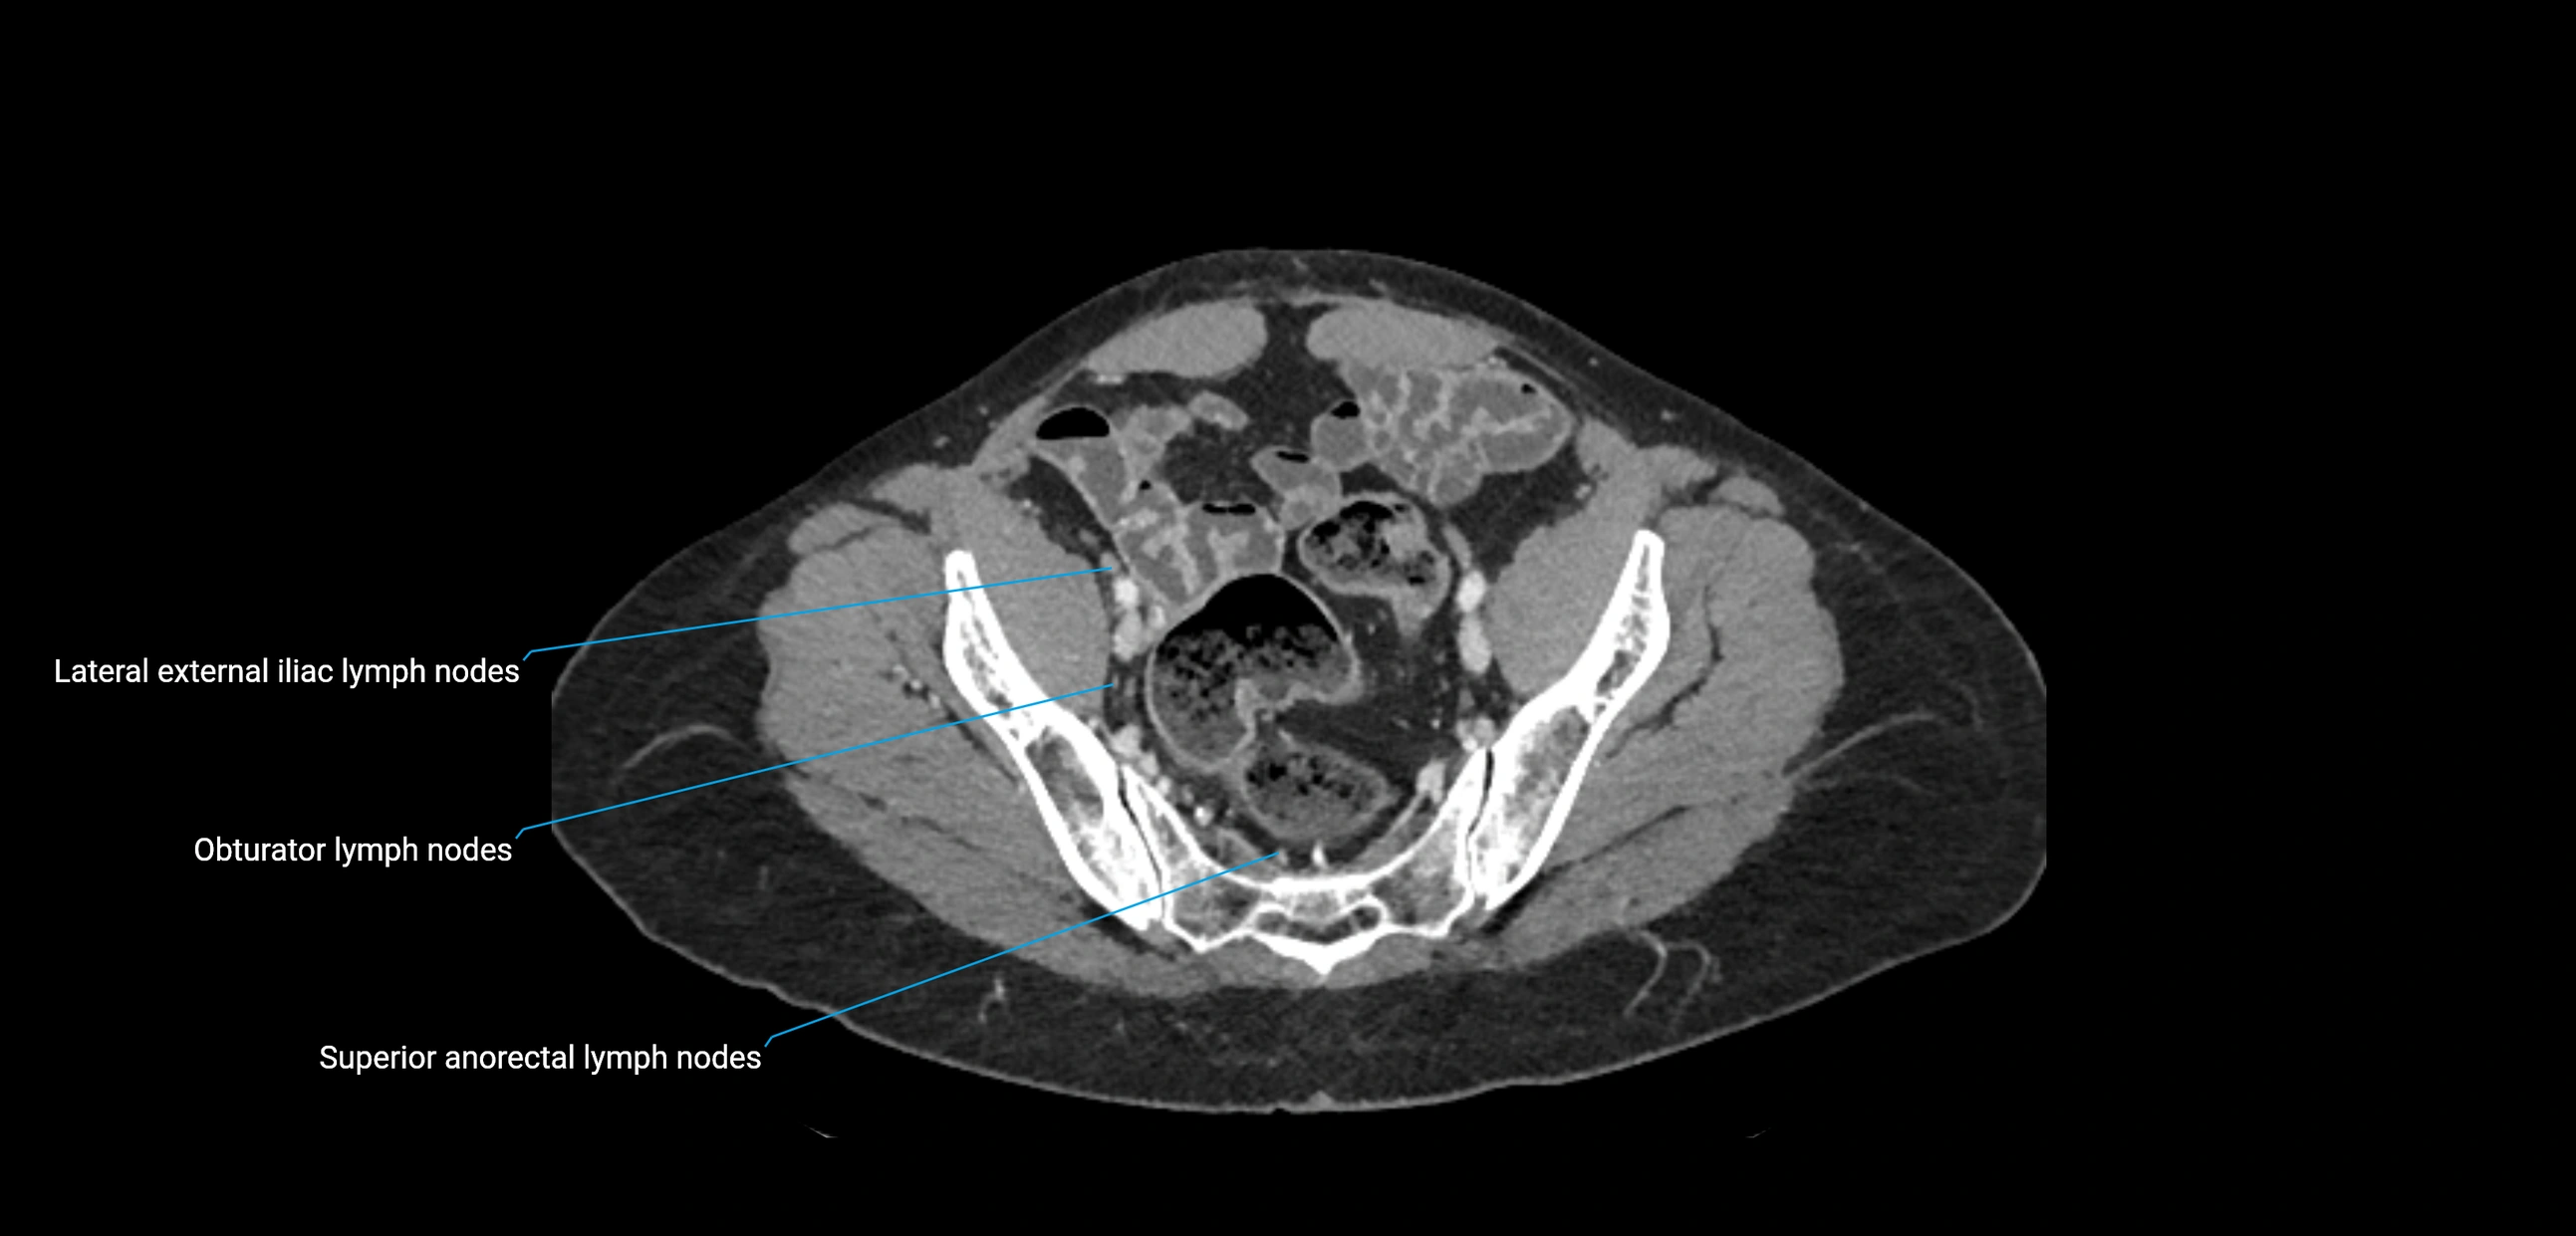

The lateral aortic lymph nodes (also called para-aortic lymph nodes) are a major group of retroperitoneal lymph nodes located along the abdominal aorta and its branches. They lie between the diaphragmatic crura superiorly and the bifurcation of the aorta at L4 inferiorly.

These nodes receive lymph from a wide range of abdominal and pelvic structures. Specifically, they drain lymph from the kidneys, suprarenal glands, gonads (testes/ovaries), uterus, uterine tubes, and pelvic organs, before converging into the lumbar lymphatic trunks, which terminate in the cisterna chyli → thoracic duct.

Clinically, the lateral aortic lymph nodes are critically important in oncology, being involved in the spread of testicular cancer, ovarian cancer, endometrial cancer, cervical cancer, renal malignancies, and retroperitoneal lymphomas. They are also key targets in retroperitoneal lymph node dissection (RPLND) for testicular tumors.

CT Appearance

CT Pre-Contrast:

• Nodes appear as soft-tissue density nodules adjacent to the aorta and IVC

CT Post-Contrast:

• Normal nodes enhance homogeneously

• Malignant nodes may show heterogeneous enhancement, central necrosis, or conglomerate formation

• Size >1 cm short axis is suspicious, though morphology and distribution are equally important